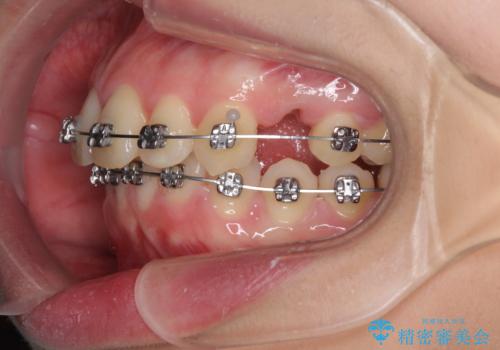

- メタルブラケット

- 3年1ヶ月

左側の咬み合わせと上下正中の位置をコントロールするために時間がかかりましたが、事前に思い描いた通りの歯列に整い、患者様には大変満足していただきました。